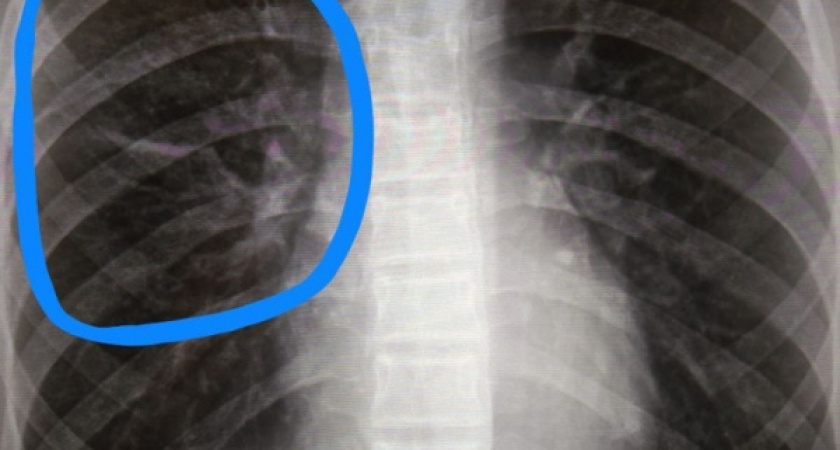

Почти половина из них была обнаружена на поздних стадиях. Врачи онкологи отмечают: чаще всего болезнь выявляется у мужчин (80% случаев), так как основными факторами риска развития этого заболевания являются хронические заболевания легких, работа с вредными химическими соединениями и курение. Риск заболеть онкологией у курящего человека в 10 раз выше, чем у некурящего. «Опасность рака легких в том, что явные внешние симптомы проявляются только на поздних стадиях. Это длительный кашель, боли в груди, кровохарканье, одышка с нарушением ритма и частоты дыхания, отёк лица и верхних конечностей, потеря веса без видимой причины», – рассказала заместитель главного врача по медицинской части Республиканского онкодиспансера Светлана Лысанова. Для того, чтобы вовремя выявить проблему, особенно тем, кто состоит в группе риска, важно регулярно – не реже 1 раза в два года - проходить такие диагностические мероприятия, как флюорография или рентген легких.